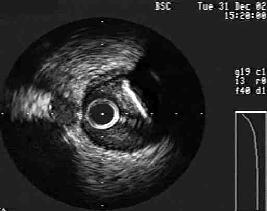

その後のIVUSではlesion distalで心筋側に、lesionにはLCx対側にcalc.があり、

plaqueはLMTにも軽度続いています。

Fig.はpreの造影と、Thrombuster後のIVUS、post CBの造影です。

IVUS-1